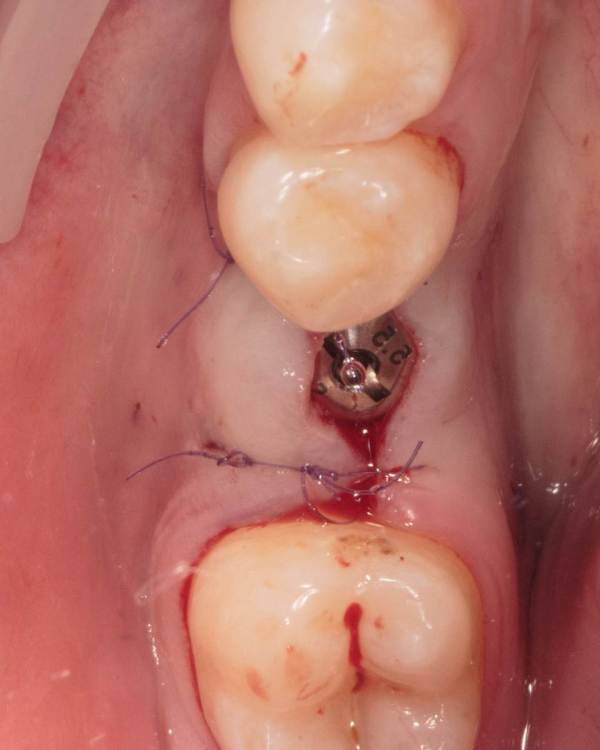

Женька Опубликовано 19 августа, 2023 Поделиться Опубликовано 19 августа, 2023 ?️. Поймал себя на мысли, что испытываю проблемы с ушиванием+ССТ на формике. А именно-не устраивает результат "прирощённой" десны. Вроде на ушивании есть + к объёму, а на протезировании "яма" вестибулярно лишь немного уменьшилась. Подскажите, как лоскут формировать так, чтобы в слоёном пироге имплантат-формик-сст оставался объём слизистой, а не таял. Подумал, что может стоит при имплантации сразу формировать асл. А в кейсе я снова "согрешил" и поставил ультра-низкий формик. В этот раз без всяких послаблений лоскута и натяжения, кмк. Ссылка на комментарий

Женька Опубликовано 21 августа, 2023 Автор Поделиться Опубликовано 21 августа, 2023 @annda да не, там всё стык в стык пассивно ушилось. скорее это потому, что "ножка" в воздухе просто висела по сути, прикрепиться не к чему, вот и до свидания Ссылка на комментарий